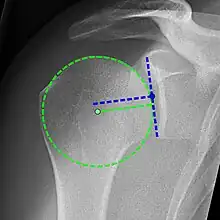

X-ray projectional radiography cannot directly reveal tears of the rotator cuff, a 'soft tissue', and consequently, normal X-rays cannot exclude a damaged cuff. However, indirect evidence of pathology may be seen in instances where one or more of the tendons has undergone degenerative calcification (calcific tendinitis). The humeral head may migrate upward (high-riding humeral head) secondary to tears of the infraspinatus, or combined tears of the supraspinatus and infraspinatus.[51] The migration can be measured by the distance between:

- A line crossing the center of a line between the superior and inferior rims of the glenoid articular surface (blue in image).

- The center of a "best-fit" circle positioned over the humeral articular surface (green in image)

Normally, the former is positioned inferiorly to the latter, and a reversal therefore indicates a rotator cuff tear.[51] Prolonged contact between a high-riding humeral head and the acromion above it may lead to X-ray findings of wear on the humeral head and acromion; secondary degenerative arthritis of the glenohumeral joint (the ball and socket joint of the shoulder), called cuff arthropathy, may follow.[50] Incidental X-ray findings of bone spurs at the adjacent acromioclavicular joint may show a bone spur growing from the outer edge of the clavicle downward toward the rotator cuff. Spurs may also be seen on the underside of the acromion, once thought to cause direct fraying of the rotator cuff from contact friction, a concept currently regarded as controversial.